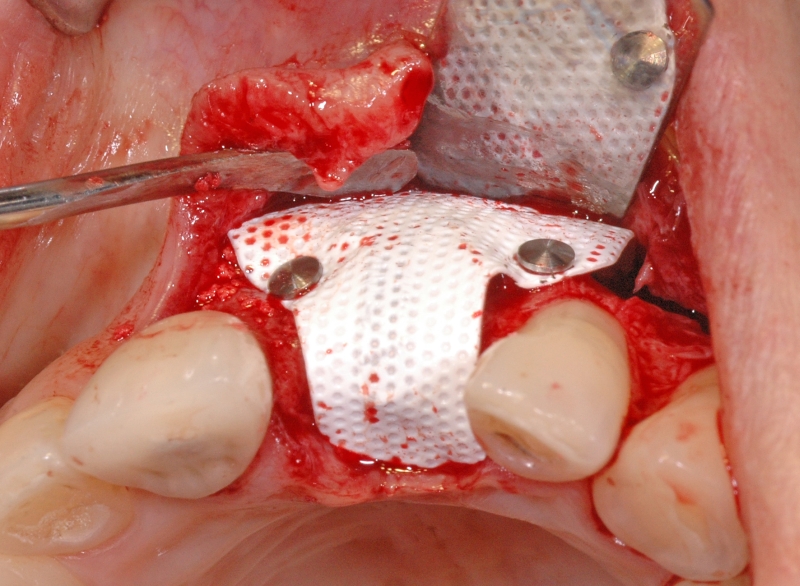

6/18 - Augmentation with maxresorb® and covering with a non-resorbable PTFE membraneGBR together with soft tissue augmentation with mucoderm® and maxresorb® - Dr. S. Scherg

7/18 - Fixation of the membrane with titanitum pinsGBR together with soft tissue augmentation with mucoderm® and maxresorb® - Dr. S. Scherg